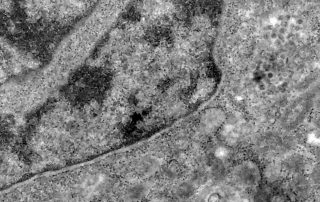

Pesquisa detecta coronavírus pela análise de retina

Estudo é desenvolvido pela Unifesp e UFRJ Pesquisadores brasileiros conseguiram, pela primeira vez, detectar a presença do coronavírus em retinas. O estudo pode contribuir para compreender melhor a dinâmica do vírus e as sequelas em pacientes infectados. A pesquisa é conduzida pela Universidade Federal [...]